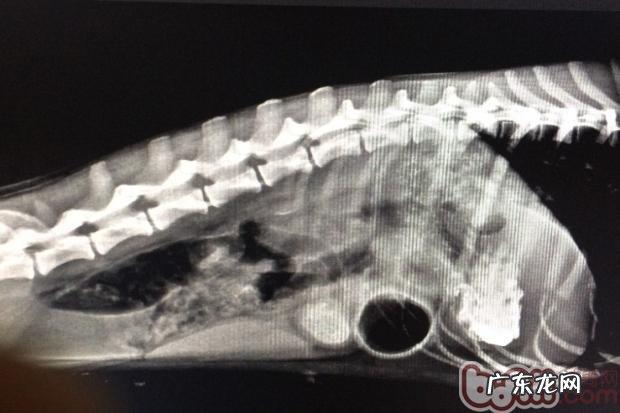

病案一:斑点犬 , 母 , 一岁半 , 今天反胃多次 , 无大便史 , 在别的宠物医院治过沒有转好 , 饮食搭配欲减少 , 触诊腹腔比较敏感 , 有一硬块 , DR显示信息肠胃有球型脏东西(见图1) , 血常规检查显示信息白细胞偏高(WBC=20.7×109/L) , 并且出現脱干(RBC↑ , HGB↑ , HCT↑) 。

图1 DR检验腹腔有一球型脏东西